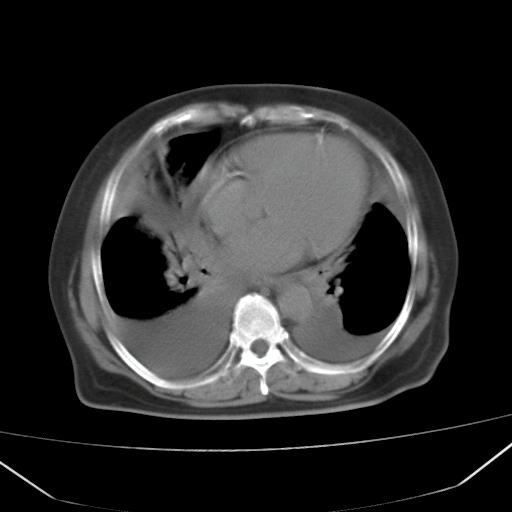

以下是引用liuyue在2008-4-19 22:25:00的发言:[br]先考虑:1.心衰伴肺水肿、双侧胸腔积液、叶间积液、双下肺不完全性肺不张; [br] 2.冠状动脉粥样硬化。

以下是引用lijuanln在2008-4-19 23:05:00的发言:[br]两侧胸腔积液,肺水肿[br]心包积液[br]提示心衰

以下是引用jiangjing在2008-4-20 10:43:00的发言:[br]结合病史支持 冠心病[冠状动脉钙化],心功能不全,肺淤血、肺水肿,双侧胸腔与斜裂积液